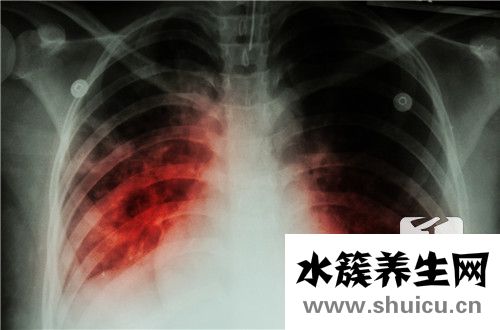

肺是非常重要的人體器官。 它可以包含通風(fēng),吸入,調(diào)節(jié)吸入,還可以促進肺部血液循環(huán)系統(tǒng)。 當(dāng)您感覺略微呼吸不暢,并且肺部感到不適時,大多數(shù)人選擇去醫(yī)院的門診進行檢查。 如果他們被診斷出肺密度低和...